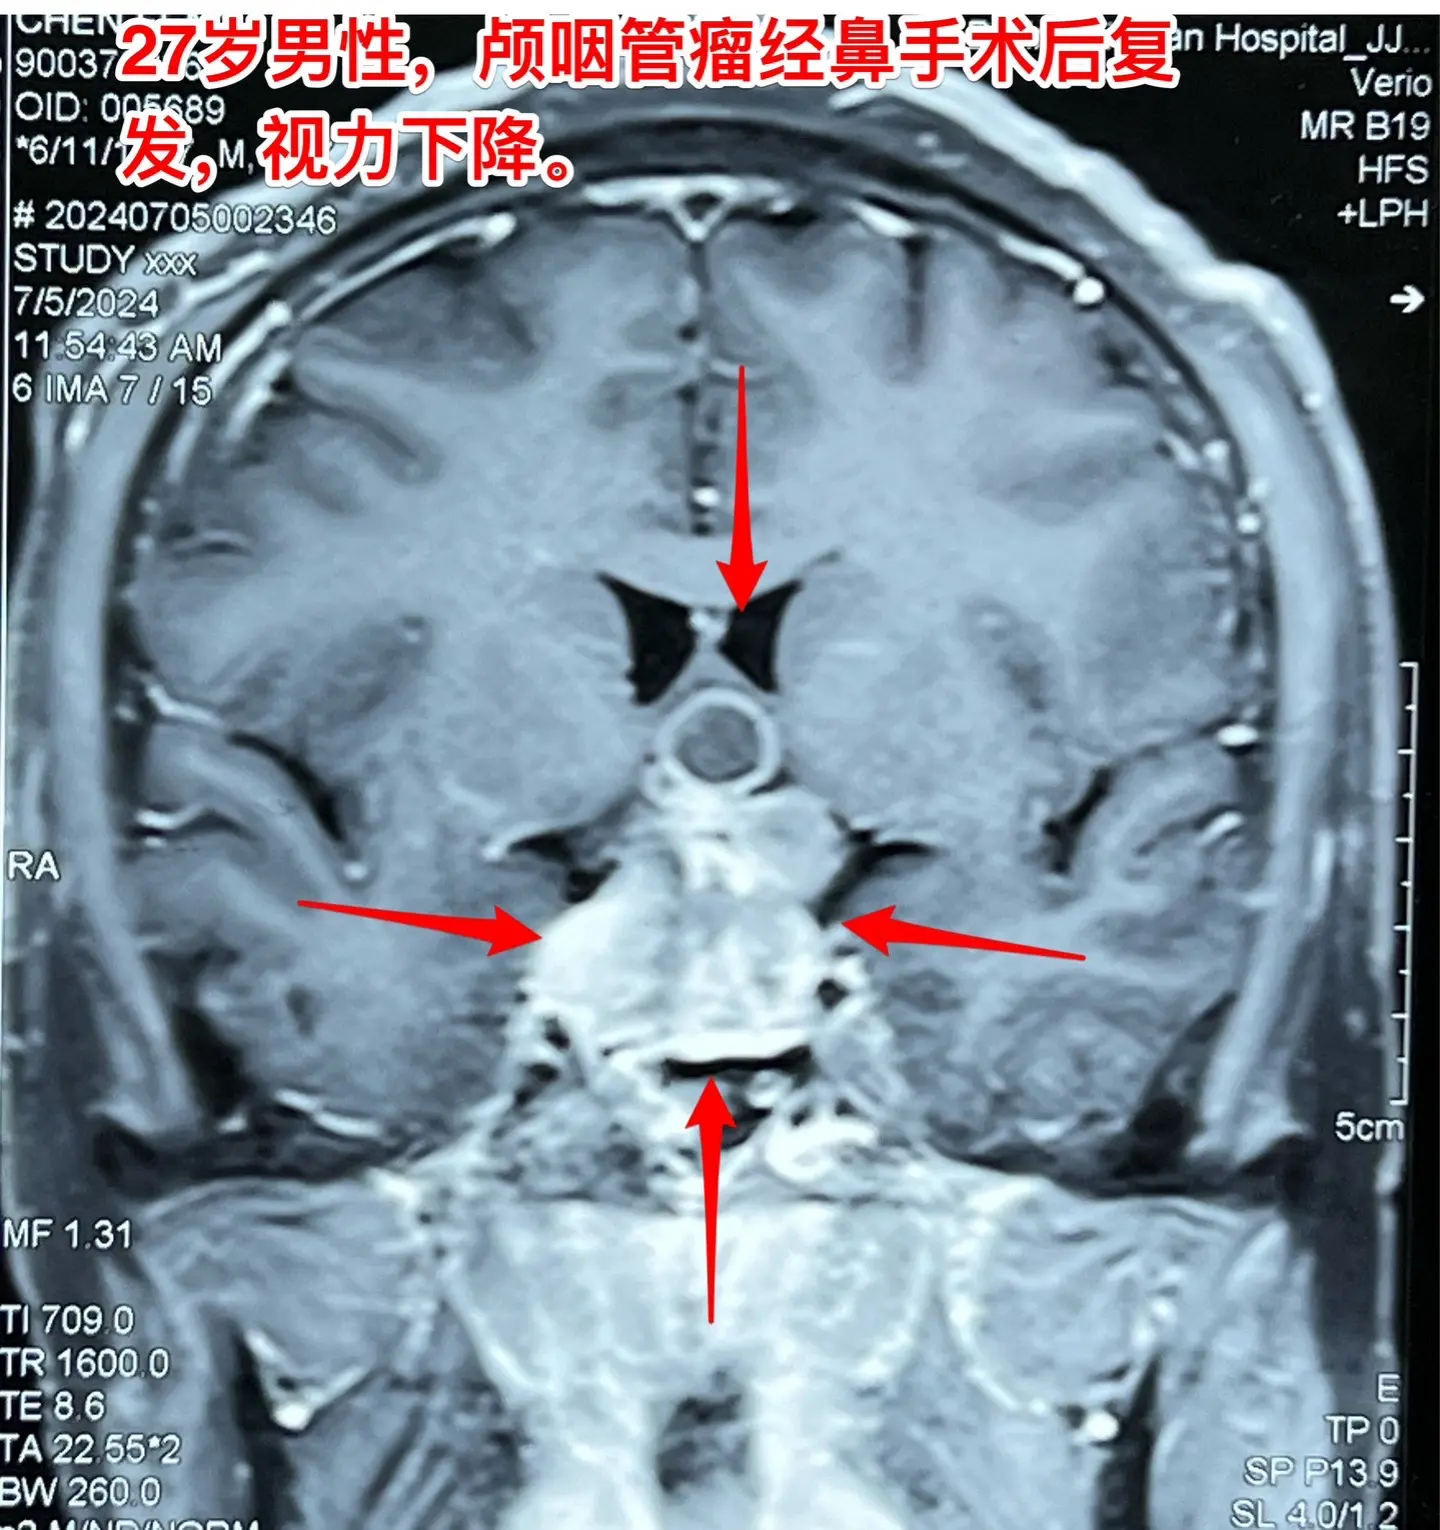

颅咽管瘤经鼻手术后8个月复发视力严重受损。27岁的甘肃小伙子因视力下降在外院诊断为颅咽管瘤,2023.11在兰州市某医院作了经鼻手术切除颅咽管瘤,肿瘤没有得到完全切除,视力稍有改善,出院后不久视力又呈下降趋势。2024年7月5日磁共振显示肿瘤体积很大。

头CT显示肿瘤密度稍高,没有钙化,见图5。患者视力很差,根本看不见视力表的第一行。看手机时手机几乎是贴着眼睛才能看见。